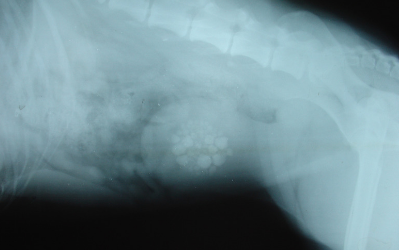

Your veterinarian may also perform X-rays to look for stones within the bladder. Unfortunately, while many types of urinary stones show up clearly on an X-ray, xanthine stones are composed of a material that is not visible. Ultrasound may be required to visualize xanthine stones within the bladder.